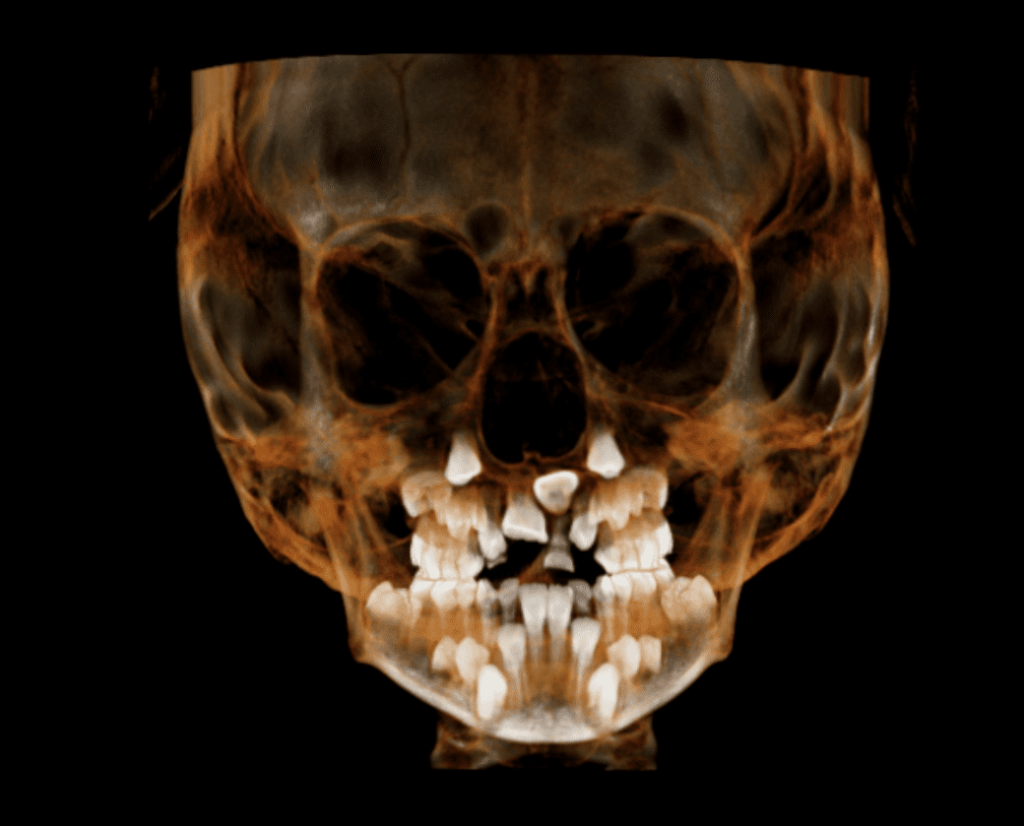

La tomografía dental completa, también conocida como tomografía computarizada de haz cónico (CBCT por sus siglas en inglés), es una técnica de imagenología avanzada utilizada en odontología para obtener imágenes detalladas de la estructura dental y ósea. A diferencia de las radiografías dentales tradicionales, que proporcionan imágenes bidimensionales, la tomografía dental completa ofrece una vista tridimensional del área de interés.

- Visualización precisa de estructuras óseas: Permite a los dentistas ver el hueso de la mandíbula, los senos maxilares y otras estructuras óseas con gran detalle, lo que es útil para planificar tratamientos quirúrgicos y la colocación de implantes dentales.

- Evaluación de la calidad ósea: Facilita la evaluación de la densidad y la calidad del hueso, crucial para el éxito de tratamientos como los implantes dentales.

- Detección de anomalías: Ayuda a identificar problemas como quistes, tumores, infecciones o problemas en la estructura dental que podrían no ser evidentes con radiografías convencionales.

- Planificación de tratamientos: Permite una planificación más precisa para tratamientos complejos, como la cirugía ortognática o la colocación de implantes, al ofrecer una visión detallada del entorno tridimensional.

- El paciente se coloca en una máquina de tomografía que gira alrededor de la cabeza, tomando múltiples imágenes desde diferentes ángulos. Estas imágenes se procesan por computadora para crear un modelo 3D de la zona a examinar. El procedimiento suele ser rápido y no invasivo, con una exposición a la radiación menor que la de una tomografía computarizada convencional.